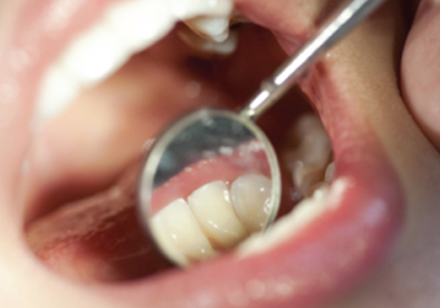

치면세균막검사로 입 속

세균과 치석 등 확인

확인된 세균과 치석 등 제거

보통 발치를 해야 하는 치아의 주변 잇몸은 세균과 염증이 퍼져 있습니다.

발치를 하는 것 만큼이나 중요한 것은 주변 치아와 잇몸의 염증 감염입니다. 발치 치아 주변의 치아와 잇몸의 염증 감염을 예방하기 위해서는 발치 전, 발치 치아의 주변을 깨끗하게 청소하고 소독하는 과정이 필요합니다. 저희는 치면세균막검사를 통해 확실하게 입속의 세균을 찾아내어 철저하게 제거합니다.